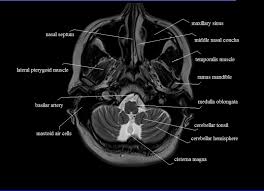

Anatomy of the brain on mri, caudate nucleus, lentiform nucleus, thalamus, ventricles radiology of brain tumors can be found elsewhere on this site, as well as brain tumor mimics. The anatomy of the brain is studied by means of axial, coronal and sagittal views. The brain, contained in and protected by the skull and suspended in cerebrospinal fluid, is one of the most important and complex organs in the body. Radiology department, rijnland hospital leiderdorp, the netherlands.